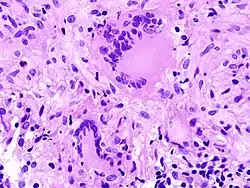

Ein erstes Abwehrbollwerk stellen spezialisierte Fresszellen (Alveolarmakrophagen) in den Lungenbläschen dar. Diese können die Erreger zwar in ihr Zellinneres aufnehmen (phagozytieren), dann aber nicht abtöten. Auch weitere herbeigerufene Fresszellen sind dazu nicht in der Lage. Der Vorgang der Phagozytose wird durch verschiedene Stoffe an der Oberfläche von Krankheitserregern aktiviert. Das können zum einen Bestandteile der Zellwand, aber auch Moleküle des Wirts sein, die sich an die Zellwand des Eindringlings gebunden haben. Mykobakterien verhindern, dass die Zellbestandteile der Fresszellen, in denen sie sich befinden, die so genannten Phagosomen, weiter reifen. Dies sichert das Überleben von Mycobacterium tuberculosis. Das Immunsystem bildet deshalb um den anfänglichen Infektionsherd einen Wall aus mehreren Ringen verschiedener Abwehrzellen. Dieser Abwehrwall aus Fresszellen (Makrophagen), so genannten Epitheloidzellen, Langhans-Riesenzellen und Lymphozyten formiert sich um einen zentralen Entzündungsherd mit Gewebsuntergang (Nekrose). Diese besondere Form der Nekrose, die auch pathognomonisch für die TBC ist, wird Verkäsende Nekrose genannt. Das gesamte Gebilde wird als tuberkulöses Granulom (oder Tuberkulom[28]) bezeichnet. Es isoliert Mycobacterium tuberculosis am Ort des Eindringens und verhindert eine Weiterverbreitung. Dazu ist ein funktionierendes Zusammenspiel der verschiedenen Abwehrzellen erforderlich, die sich gegenseitig über verschiedene Botenstoffe (Zytokine) herbeirufen und aktivieren. Insbesondere die Ausschüttung von Tumornekrosefaktor sorgt für nitrosativen Stress im Phagosom, der zusammen mit der Einkapselung das Bakterium zwingt, in einen Ruhezustand überzugehen.[29]